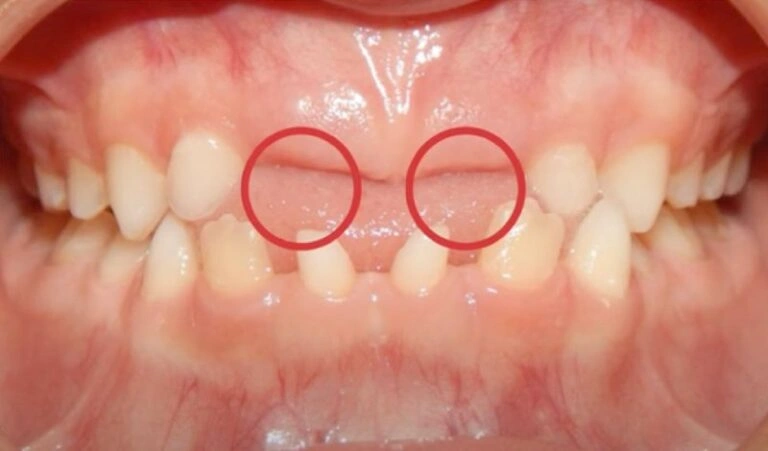

In some cases, the roots of the baby teeth don’t dissolve as they should, keeping them firmly in place. If the permanent tooth beneath isn’t growing in straight, it won’t apply enough pressure to push the baby tooth out. We often see this in kids with crooked or crowded teeth. A quick X-ray can tell us if this is the issue. See the case of Barret, a pediatric patient of mire below!

3. Crowding Issues

This is one of the most common reasons I see, and it’s something we should address early! If there isn’t enough space in your child’s mouth for their adult teeth to come in, the baby tooth can get stuck in place. As a result, the adult tooth might grow in behind or on top of the baby tooth, making things even more complicated.